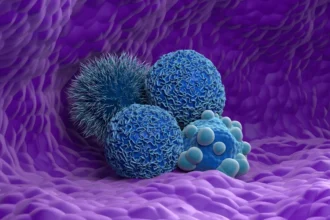

Novo medicamento aumenta sobrevida em câncer de pâncreas. Entenda

Um medicamento experimental pode ajudar pacientes com câncer de…